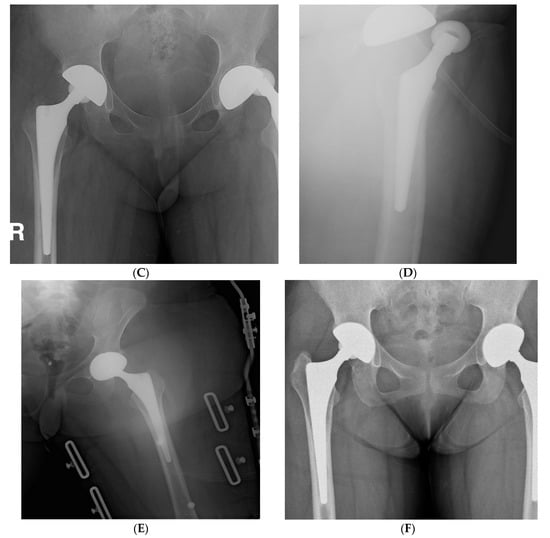

Figure 3.

(A) Preoperative hip radiograph of a 41-year-old man who had undergone surgical removal of meningioma in the right frontal lobe 4 years prior to THA, demonstrating collapsed osteonecrosis of the right femoral head. (B) Five-year postoperative radiograph demonstrating stable implants with Brooker grade 2 heterotopic ossification. The patient had no pain and was satisfied with the outcome.